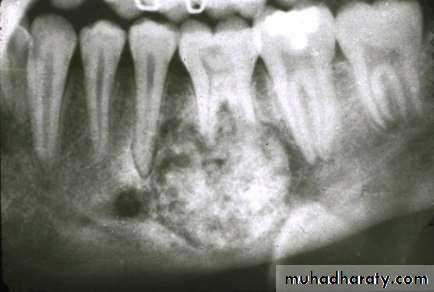

• Radiography:• Uni or Multilocular radiolucent areas

• Soap bubbles

• Copyright 2003, Elsevier Science (USA). All rights reserved.• Ameloblastoma

• Radiography:

• Soap bubbles appearance